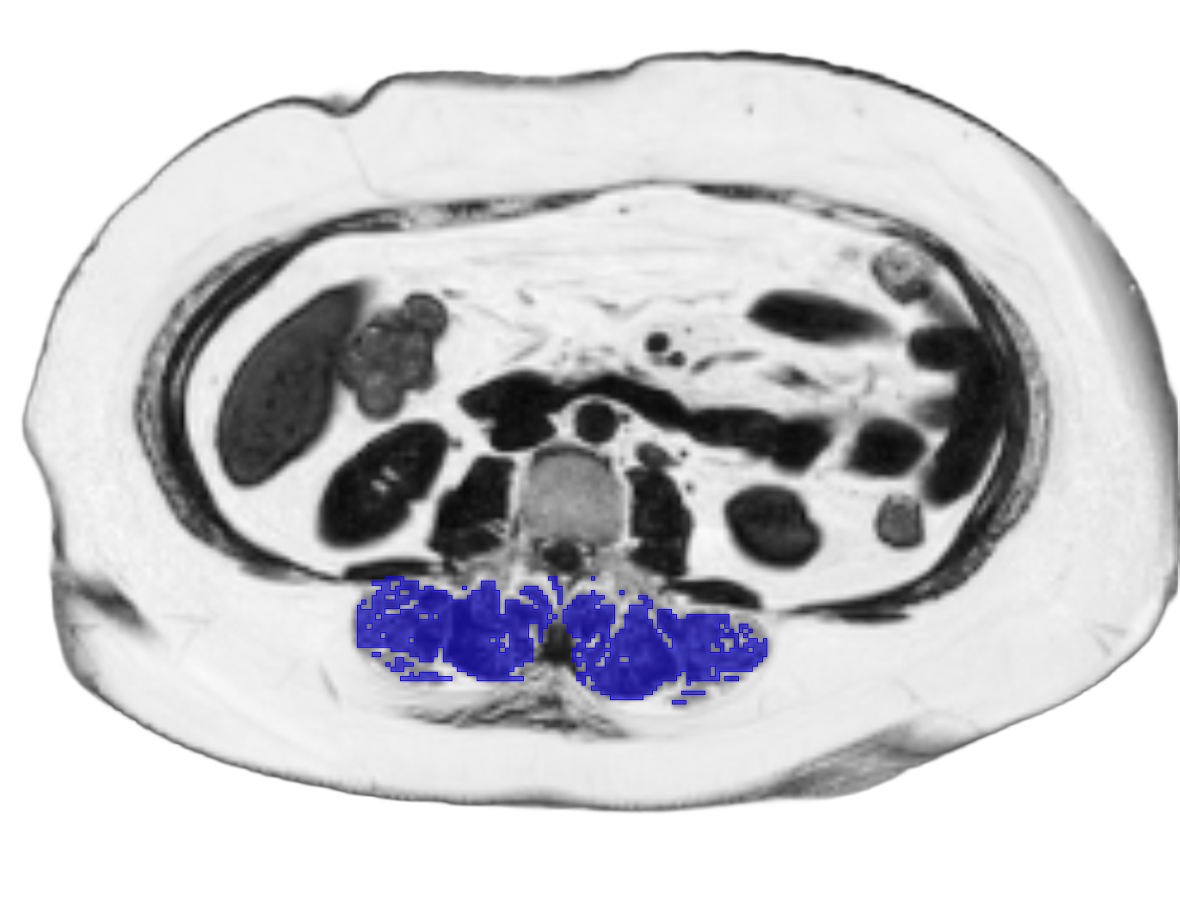

We provide neck-to-knee MRI body composition metrics including visceral (VAT) and subcutaneous adipose tissue (SAT), lean tissue volume, skeletal muscle volume and index, muscle fat infiltration (MFI), and suspected brown adipose tissue (sBAT).

Muscle volume and muscle fat infiltration – critical indicators of quality weight loss and overall health

MRI body composition